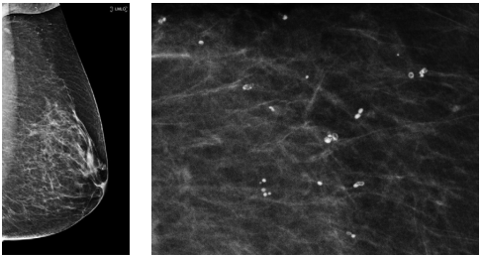

Dermatomyositis

autologous fat injection

deep oil cysts bilaterally - a lot of them

what bir-rads?

BR-2. multiple popcorn (dystrophic) calcs = multiple degenerating fibroadenomas